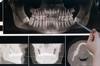

However, immediate implant placement is not suitable for everyone. Success depends on several factors, including the health of the extraction site, the quality and quantity of available bone, and the patient’s overall oral hygiene. For instance, infections or significant bone loss at the extraction site may necessitate a delayed approach. Dentists often use cone-beam computed tomography (CBCT) scans to assess bone density and plan the procedure meticulously. Patients must also commit to rigorous post-operative care, including avoiding hard foods and maintaining impeccable oral hygiene to ensure the implant integrates successfully.

Anatomical considerations further refine candidate suitability. The extraction socket’s shape and size must align with the implant’s dimensions. A socket that is too narrow or irregular may require grafting or delayed implantation. Similarly, the presence of infection or active periodontal disease in the extraction site is a contraindication. Such conditions necessitate prior treatment to create a healthy environment for implant integration. Radiographic analysis, including cone-beam computed tomography (CBCT), is essential to assess these factors and guide decision-making.